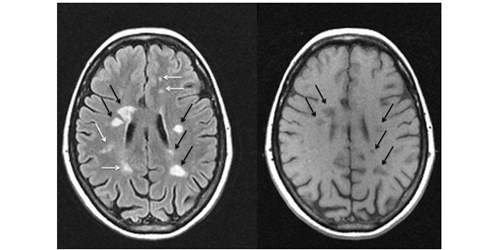

Пройти МРТ головного и спинного мозга.

Это главный инструмент для постановки диагноза. С помощью МРТ можно обнаружить участки измененной плотности в белом веществе головного мозга.

Магнитно-резонансные томограммы головного мозга пациента с рассеянным склерозом в разных режимах съемки. Черными и белыми стрелками показаны очаги демиелинизации (бляшки).

Регулярные МРТ-исследования у пациентов с РС позволяют распознать первые признаки необходимости смены тактики лечения.